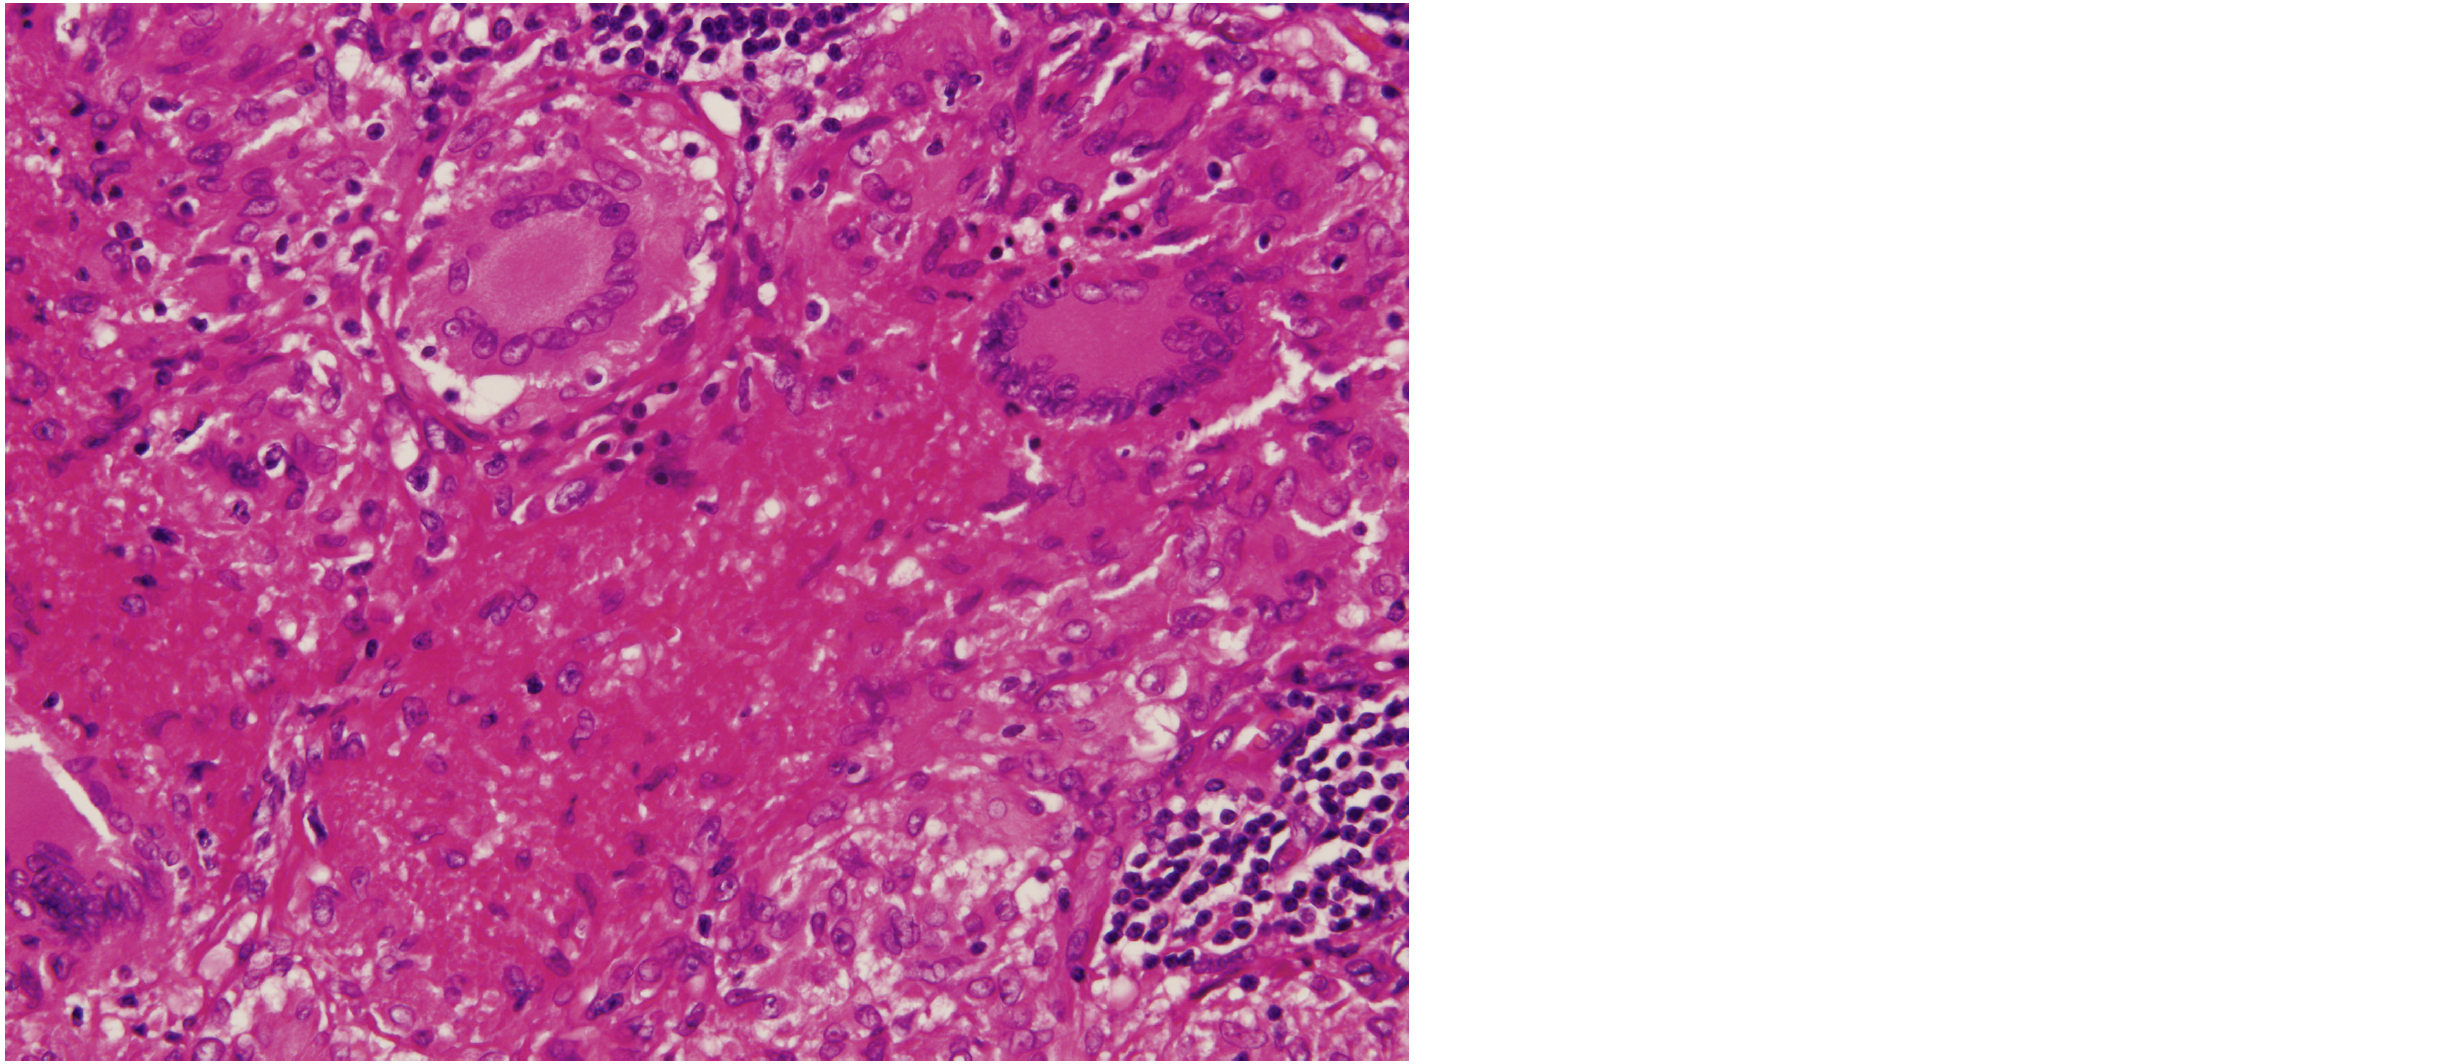

H-E 染色標本を示す。

炎症の種類はどれか。

1. 化膿性炎

2. 出血性炎

3. 漿液性炎

4. カタル性炎

5. 肉芽腫性炎